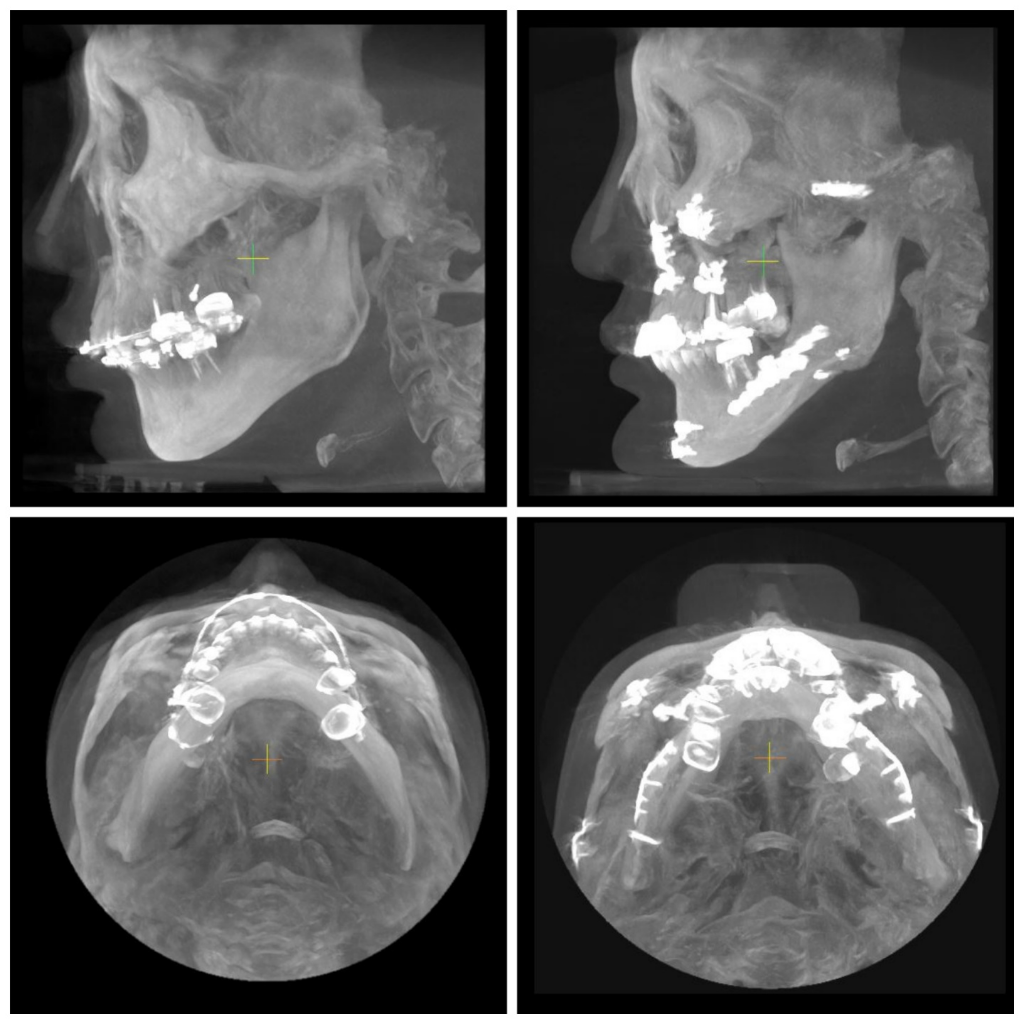

수술 후 제 뼈가 이상한것 같은데 제눈이 이상한건가여?

얼굴형부터 중심선까지 너무 틀어져서요

한쪽이 치아도 그렇고 뒤로 빠져있어요,

근육은 그렇다 쳐도 뼈는 맞춰서 수술해 줘야 하는거 아닌가요?

목구멍? 기도도 답답한 느낌이예요..

뼈가 맞춰져 있는데 근육이 비대칭이라서

(핀제거도 다 했어요, 중심이 안맞는것, 교합 좀 봐주세요)